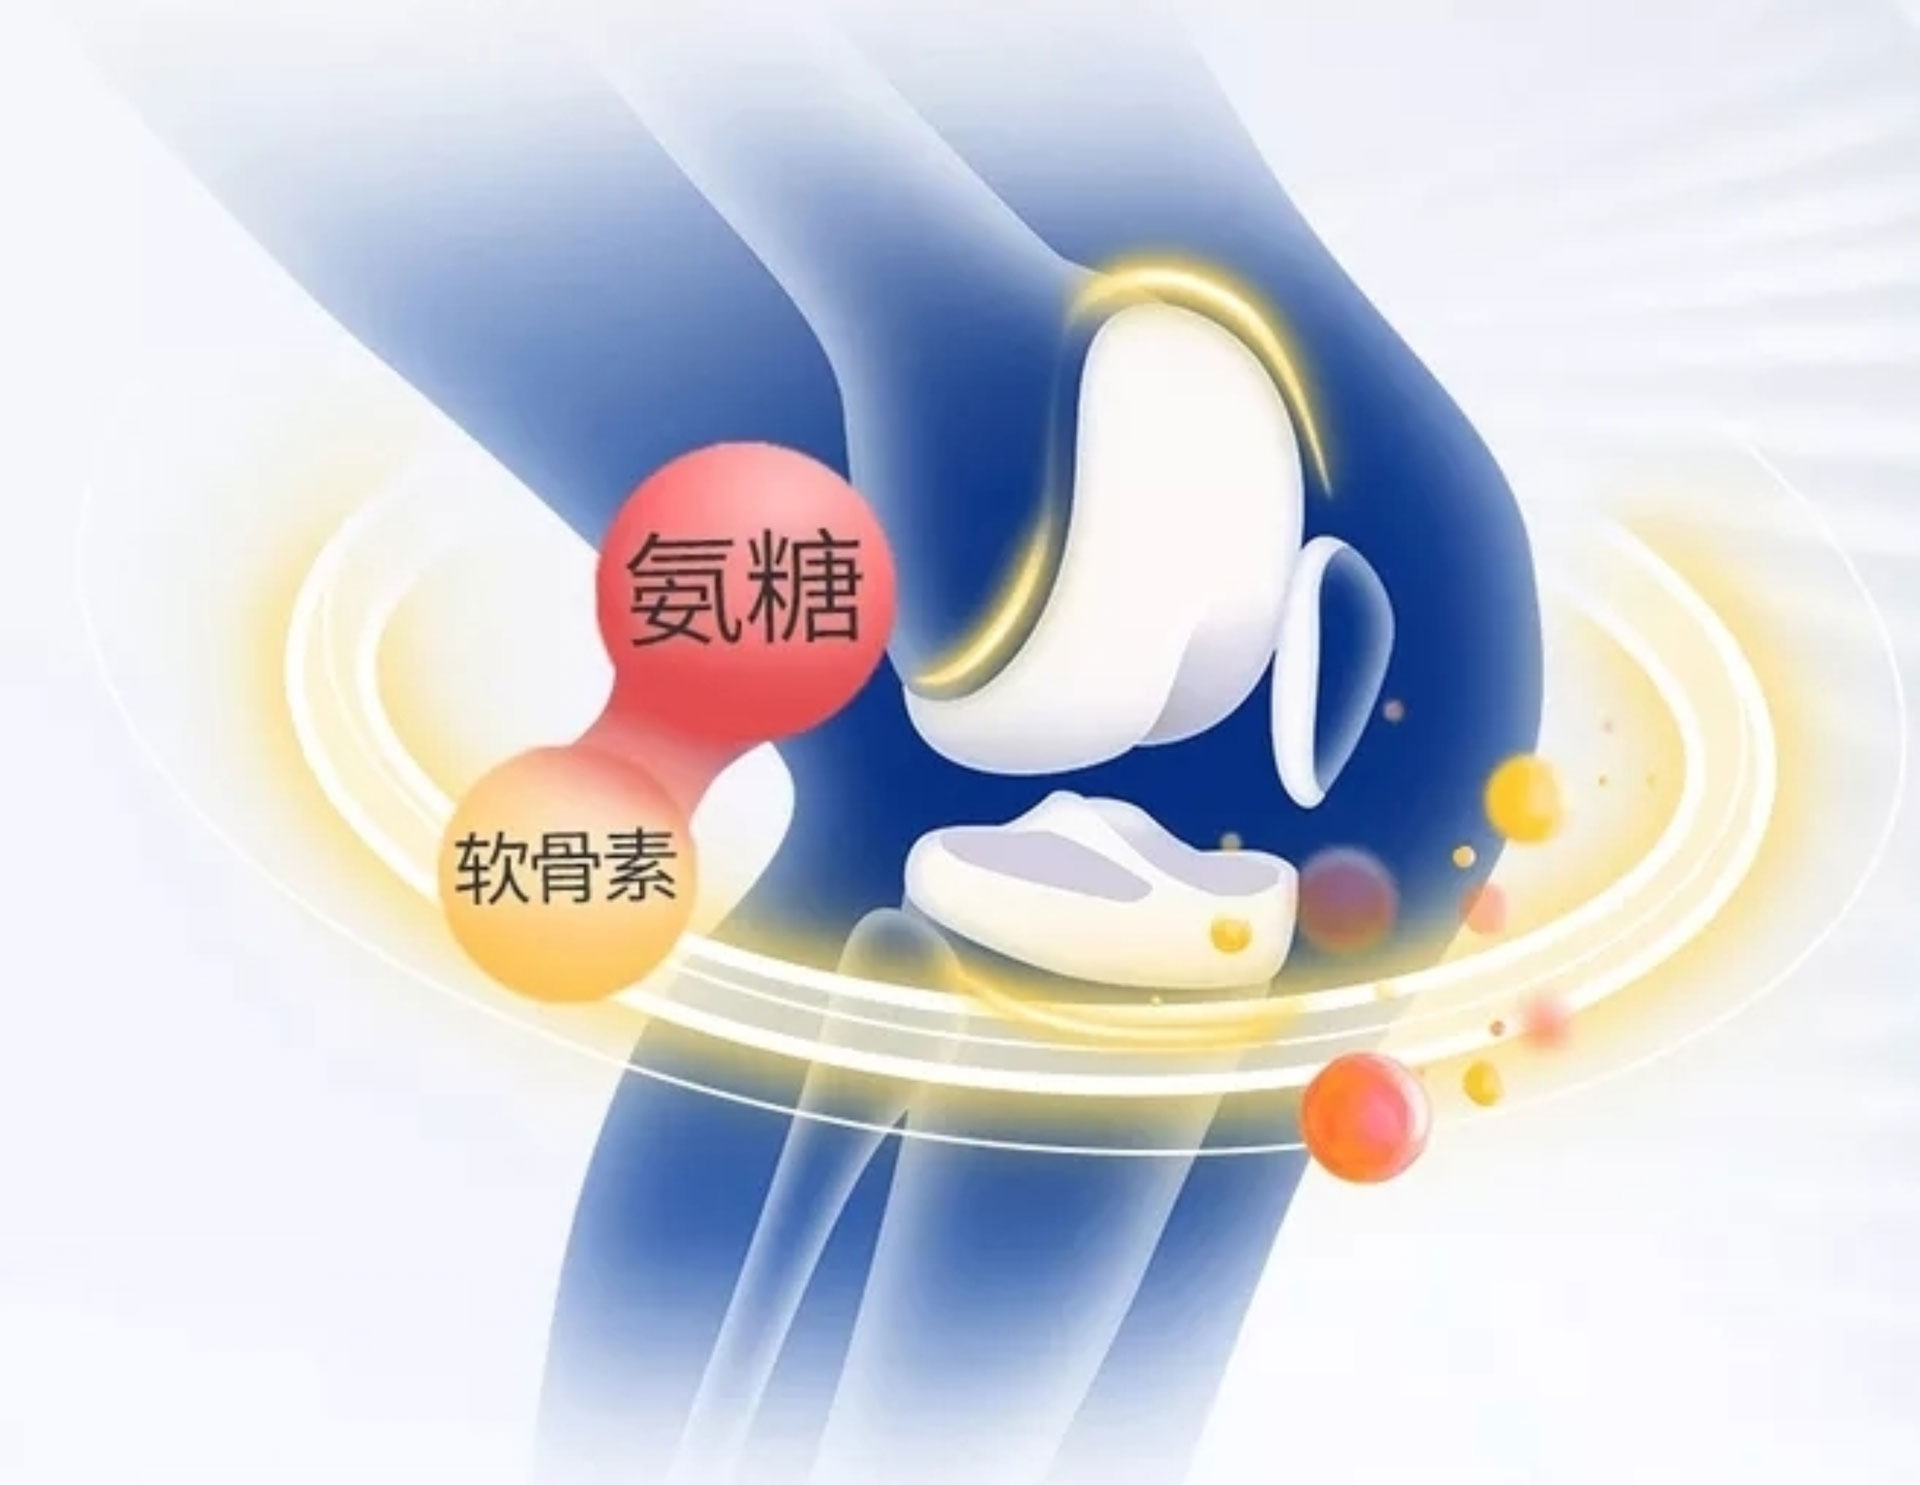

氨基匍萄糖又被粉丝称为匍萄糖胺,名字简称氨糖,是亲水较强的血清多糖的注重构成的方面,是确立软骨生殖细胞的注重菅养素一个,也是软骨大体材料和软骨液的大体成分表。

简简单单来讲,氨糖是环节的守护神~~

氨糖的能力